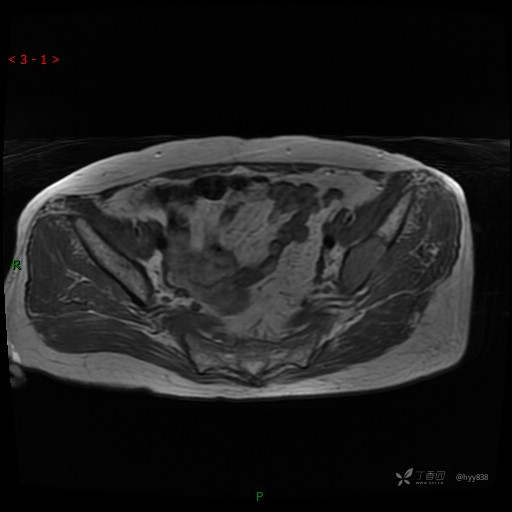

MRI T1WI+T2WI axi